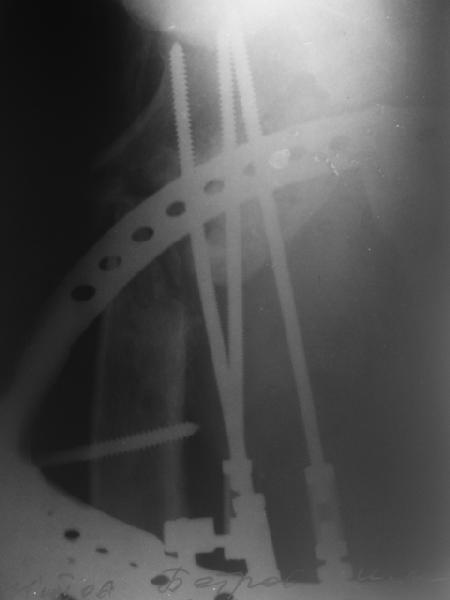

В приложении пример пациента, близкого по картине к тому, что

представил Виктор (варус и смещение периферического отломка на

поперечник кзади). Сделали как раз то, что Виктор исходно намеревался

- аппаратная коррекция и затем гамма.